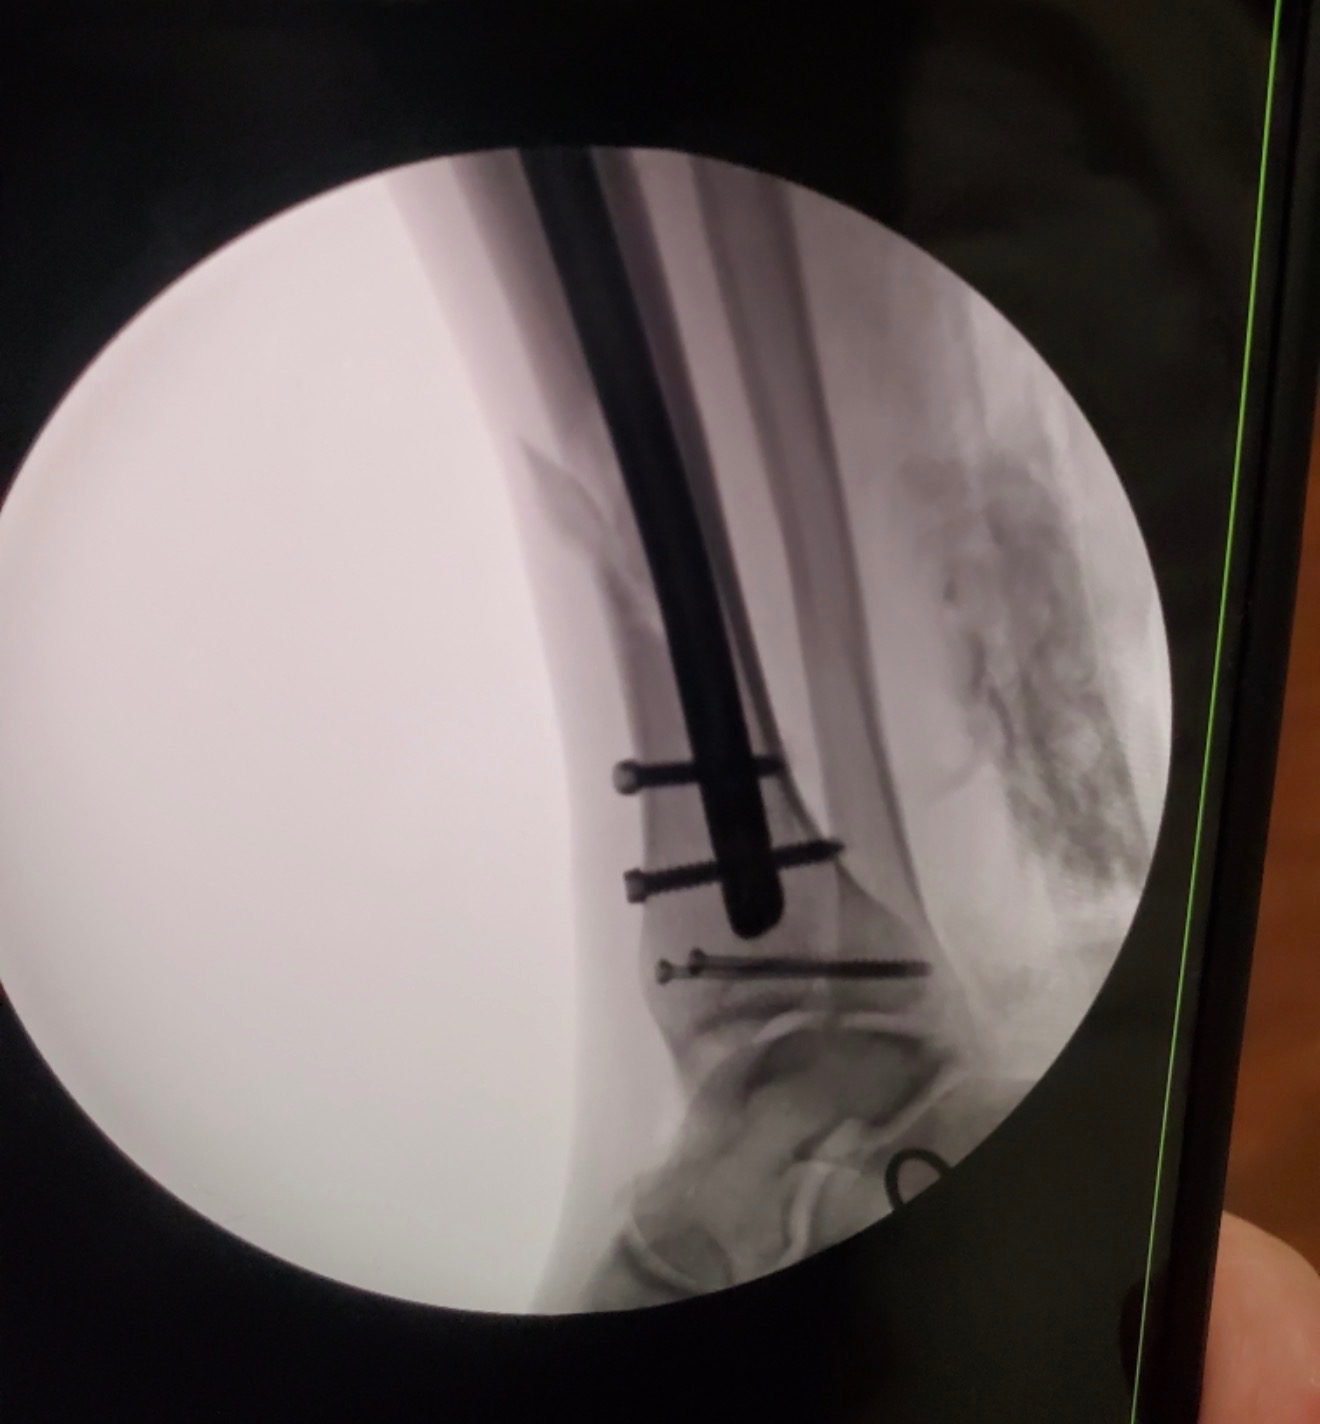

We are reaching out during an incredibly difficult and unexpected time for our family. My stepdad, Joseph, was recently involved in a serious motorcycle accident after hitting a deer at approximately 65 miles per hour. We are beyond grateful that his injuries were not life-threatening, but he did suffer a severe leg injury that required surgery, including rods placed in his leg and screws in his ankle.